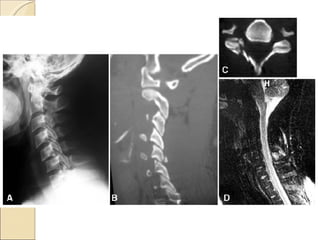

Illustrative Case No. 1 17 y/o female patient Presented after 30-foot-fall with severe neck pain. Neurological examination was normal.

CT: Burst fracture of C-7 vertebra MRI: Normal signal intensity of disc and both the anterior and posterior ligamentous structures

Total SLIC score = 2 Non-surgical treatment

Illustrative Case No.1 17 y/o female patient Presented after 30-foot-fall with severe neck pain. Neurological examination was normal.

CT: Burst fractureof C-7 vertebra MRI: Normal signal intensity of disc and both the anterior and posterior ligamentous structures

Total SLIC score= 2 Non-surgical treatment